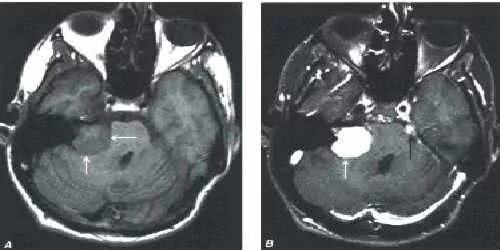

Мрт головного мозга мосто мозжечкового угла